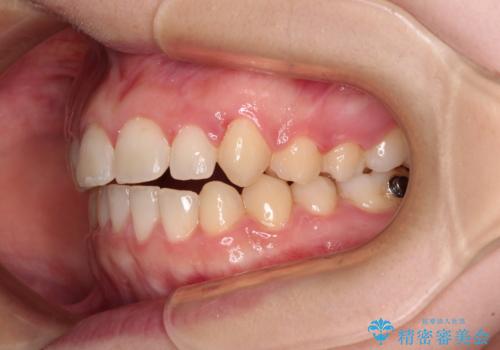

- 八重歯を気にして来院された患者様です。

八重歯のために乳歯が残存していたため、乳歯を抜去して八重歯となっている犬歯を歯列に収めることとしました。

八重歯の移動量が多くなるため、インビザラインと併用してワイヤー矯正を行い、八重歯を改善した後に、上下歯列をインビザラインで整えることとしました。

犬歯は歯根が長くて太いため移動に時間がかかる上に、周囲の歯が八重歯に寄ってきてしまうため、仕上がるまでに期間がかかりました。